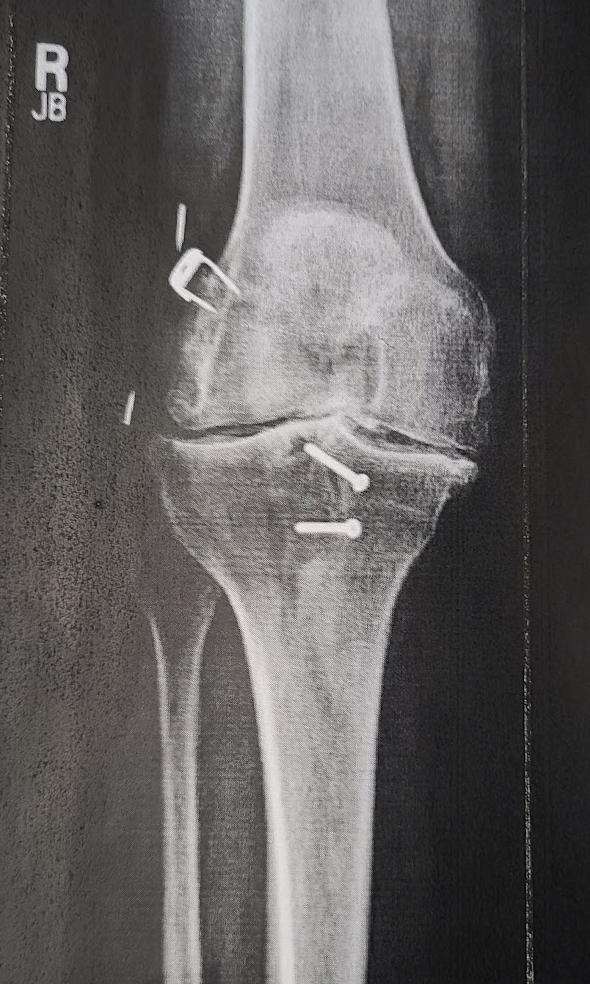

Brooks is working me! My day job provides free gym membership so I joined 10 Fitness in Paragould. Because of my no-ligaments-no-cartilage-bone-on-bone knees (check out that xray from 10 years ago), Brooks has me with low weights and high reps (40 reps, then, 30 reps). There is a study saying as long as the muscles are taxed, the ratio of weight vs reps doesn’t matter.